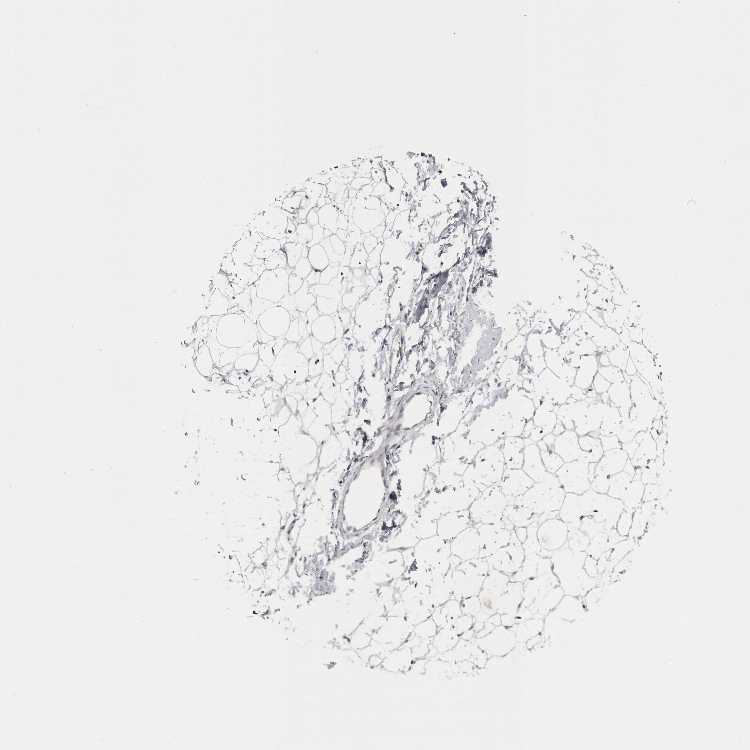

ADIPOSE TISSUE - Antibody stainingi

Antibody staining in the annotated cell types in the current human tissue is reported as not detected, low, medium, or high, based on conventional immunohistochemistry profiling in selected tissues. This score is based on the combination of the staining intensity and fraction of stained cells.

Each image is clickable and will lead to virtual microscopy that enables deeper exploration of all samples and also displays staining intensity scores, fraction scores and subcellular localization as well as patient and tissue information for each sample.

Antibody HPA026874Antibody HPA061426

Adipocytes Not detectedNot detected